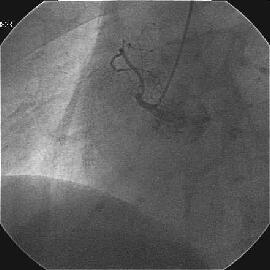

�܂�pre CAG.

|

|

|